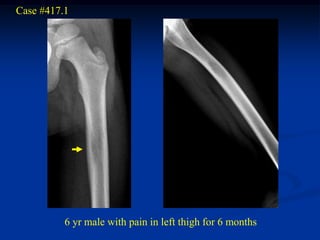

Case #417.1

6 yr male with pain in left thigh for 6 months